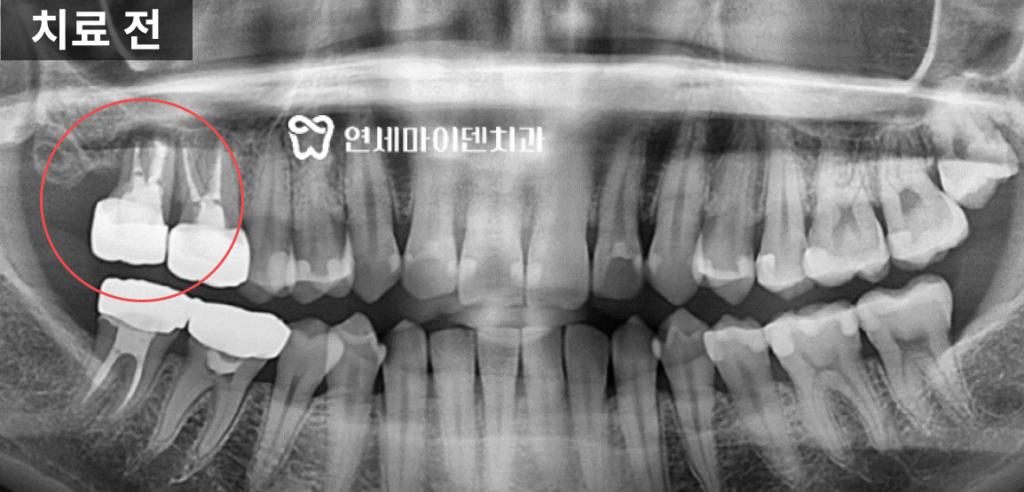

아래쪽 어금니가 심하게 흔들리고 있었고,

손으로 살짝만 힘을 줘도 빠질 정도로

뼈가 많이 녹아 있었던 상태였습니다.

문제는 발치를 하더라도

하치조 신경관과 너무 가까운 위치이기 때문에임플란트를 심기 어렵다는 진단을

타원에서 받으신 겁니다.실제 엑스레이 상으로도

치아 뿌리 주변의 치조골이 까맣게 소실돼 있었고,신경관이 바로 인접해 보이는 모습이 관찰되었습니다.

엑스레이는 2차원적인 단면 영상이기 때문에

치조골 상태를 입체적으로 파악하기에는 한계가 있습니다.정확한 진단을 위해 3D 네비게이션 CT 촬영을 진행했습니다.

입체적 영상으로 확인한 결과,

입 안쪽 잇몸뼈는 많이 소실돼 있었지만

치조골 외측에는 하얗게 뼈가 남아있는 부분이 존재했습니다.단면 영상으로는 전혀 식립 공간이 없는 것으로 보였지만,

실제로는 바깥쪽 잇몸뼈가 충분히 남아 있었던 것입니다.또한 하치조 신경관과의 거리도 확보할 수 있어서

임플란트 식립이 가능한 상태임을 확인할 수 있었습니다.따라서 발치 즉시 임플란트 식립을 진행하기로 하였습니다.